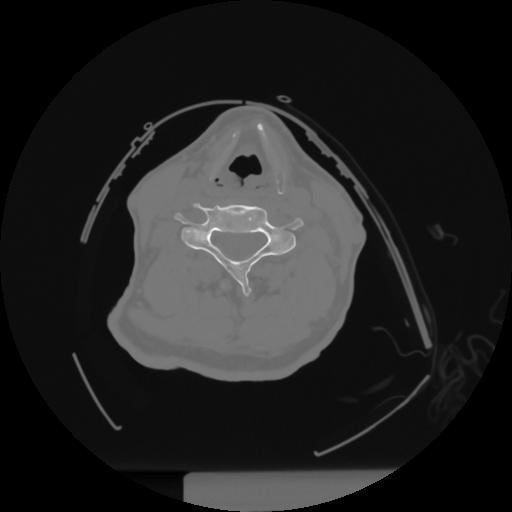

12 P.BLANDAS,,Vol,0.5,P.BLANDAS,,